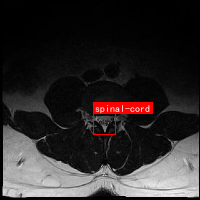

图2展示了我们改进的YOLO11模型架构。该模型在保持原有检测速度优势的同时,通过引入SCcConv注意力机制,显著提升了对脊髓区域的检测精度。图中红色框标出了我们新增的SCcConv模块,它能够在特征提取过程中自适应地关注脊髓区域的重要特征。